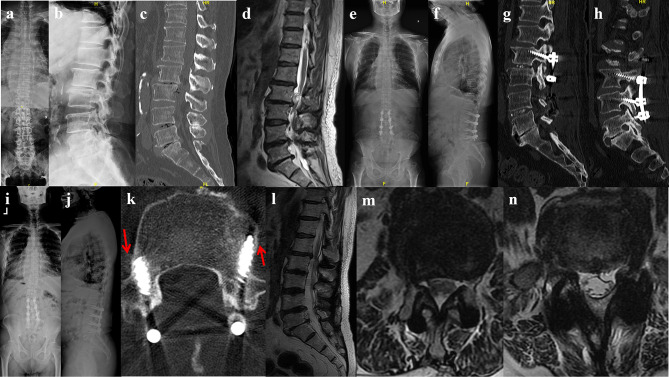

Patients and methods: From January 2018 to December 2019, a total of 41 patients of mild adult degenerative scoliosis with stenosis underwent posterior lumbar decompression, bone graft fusion, and internal fixation, which were retrospectively divided into pedicle screw (PS) group and cortical bone trajectory (CBT) screw group according to different internal fixation methods. The operation time, intraoperative blood loss, immobilization, and length of hospital stay were compared between the two groups. The visual analog score (VAS) of low back and leg pain, Oswestry disability index (ODI), Cobb angle, lumbar lordosis (LL) angle, apex vertebral translation (AVT), coronal balance distance (CBD) and sagittal vertical axis (SVA) were compared between the two groups preoperatively and 6 months, 1 year, 5 years postoperatively. Perioperative and follow-up complications were observed.

Results: The CBT group was superior to PS group in operation time, intraoperative blood loss, immobilization, length of hospital stay (P<0.05). The low back VAS and ODI in CBT group were significantly lower than those in PS group at 6 months, 1 year and 5 years postoperatively (P<0.05). The leg VAS in CBT group was lower than PS group at 5 years postoperatively (P<0.05). The incidence of screw loosening and adjacent segment disease 5 years postoperatively in CBT group was significantly lower than that in PS group (P<0.05).

Conclusion: Multi-segment cortical bone trajectory screws is a safe and effective treatment option for mild adult degenerative scoliosis with stenosis among the elderly. This technique features miniinvasive trauma and quick recovery, which might lead to improved long-term quality of life and a reduction in screw loosening and adjacent segment disease rates.